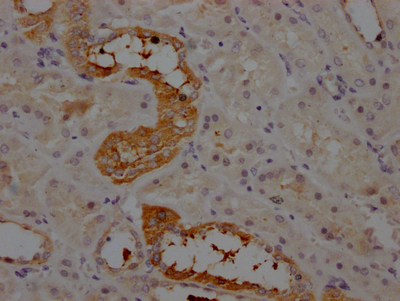

AGT Recombinant Monoclonal Antibody (CSB-RA263831A0HU)

IHC image of CSB-RA263831A0HU diluted at 1:100 and staining in paraffin-embedded human kidney tissue performed on a Leica BondTM system. After dewaxing and hydration, antigen retrieval was mediated by high pressure in a citrate buffer (pH 6.0). Section was blocked with 10% normal goat serum 30min at RT. Then primary antibody (1% BSA) was incubated at 4℃ overnight. The primary is detected by a Goat anti-rabbit IgG polymer labeled by HRP and visualized using 0.05% DAB.